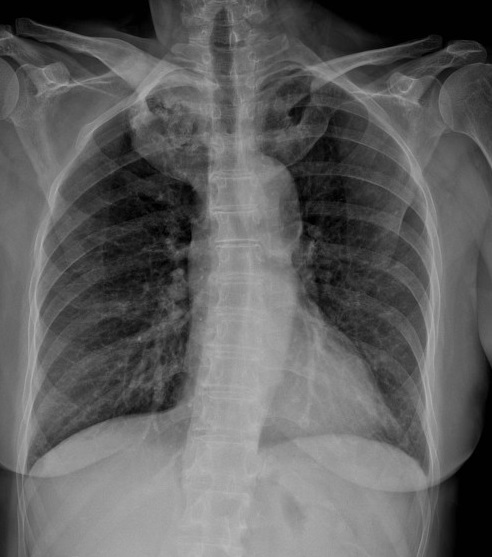

Image radiologique pulmonaire

AP d'une syndrome de SAPHO avec image de tumefaction

de osteite et hyperostose de articulation

sternoclaviculaire droit et gauche |

|

Même cas est en agrandissement |